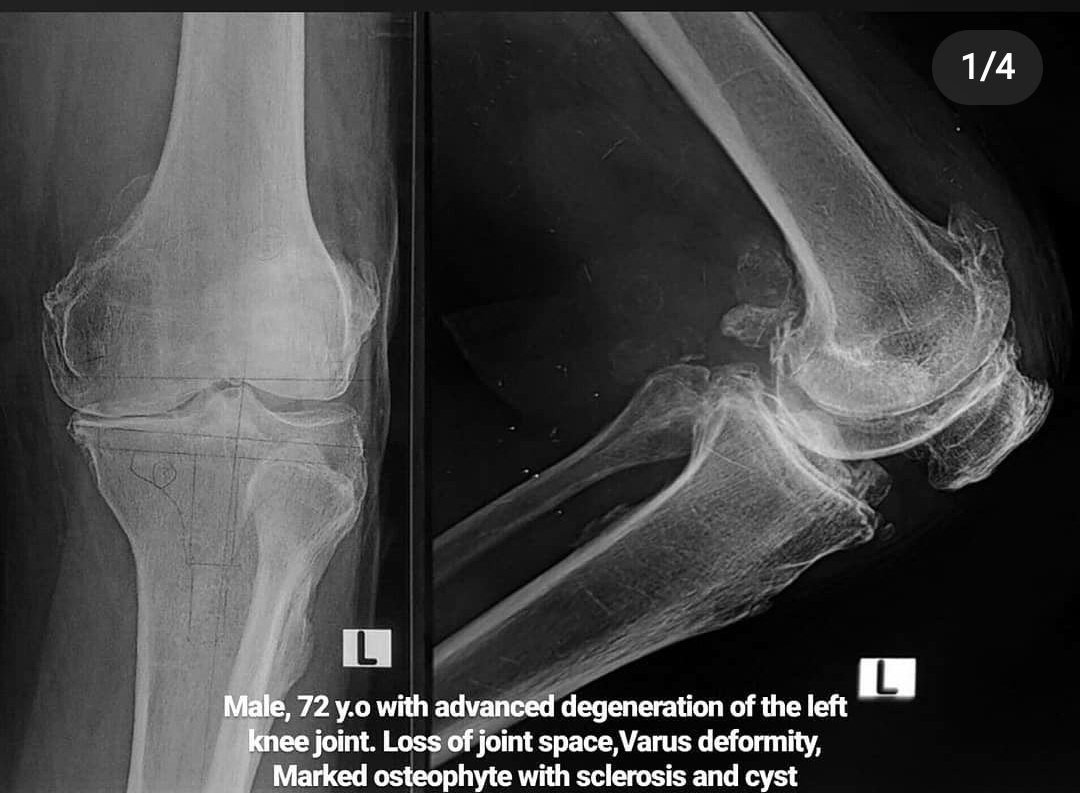

pada kasus yang berat,obat&semua mcm cara ud ga bisa lagi utk mengurangi sakit pasien,ngapa2in sakit, kasusnya uda parah, pada kasus yg sudah seperti ini, pilihan yg paling tepat adalah operasi, operasinya adalah operasi TKR (total knee replacement ) ,atau penggantian sendi lutut

Pastikan OA nya separah apa dulu,dgn pemeriksaan dan ronsen.

dan ditangani tergantung keparahan

Kalo uda parah ya mau dikasi obat terus ya ga akan sembuh,karena mungkin harusnya sendinya uda harus diganti

Sebaliknya,kalo masi ringan,byk yg bisa membaik bgt dgn obat,turun BB,fsioterapi, dan mungkin dgn tambahan suntik lutut ..